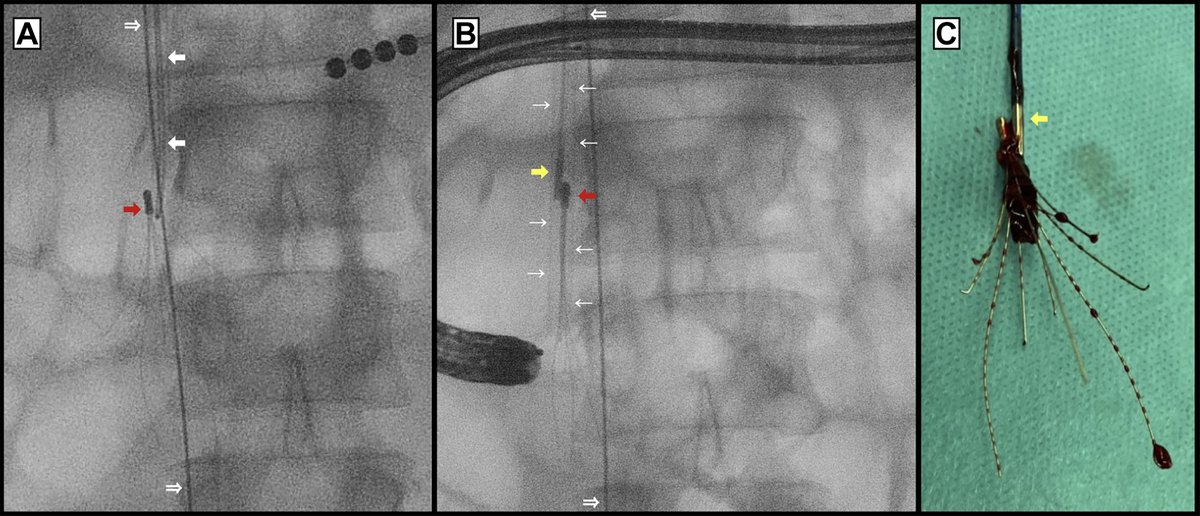

This #IVCfilter was placed after a #trauma in a patient with DVT. During removal, the apex was imbedded and removed with standard equipment using the “hangman” aka “loop sling” technique of flossing a glide wire through the apex #iRad

20yr M, 2 yr old filter with tilt and embedded tip. Corrected with snare over loop technique and captured filter in sheath #FilterOutFriday #FilterOut #IVCFilter #DVT #PE #TiltedFilter